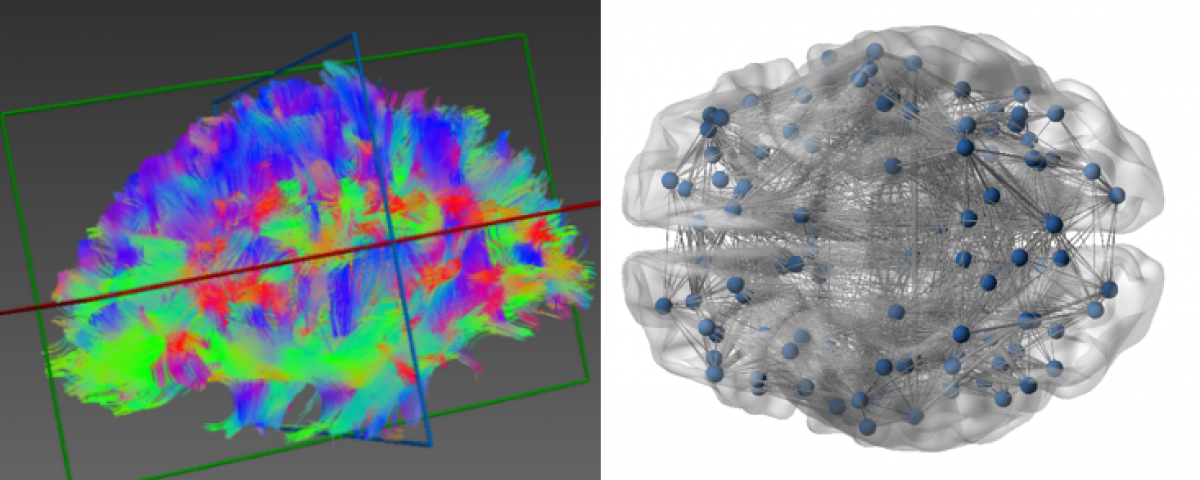

- DeepMIA (Deep Learning and Medical Image Analysis Laboratory)

https://deepmia.bogazici.edu.tr/

Areas of Study: He uses Deep Learning, image processing and computer vision techniques to solve problems in the field of artificial intelligence in health. She develops multi-modality artificial intelligence models by combining clinical data, histopathology and radiology images and genetic information of the patient.

Deep learning based tissue segmentation, Classification and grading in various cancer types and non-cancerous diseases, Artificial intelligence based survival analysis, Prediction of patients who develop treatment response, drug resistance or side effects, Synthetic image generation for histopathological staining and contrast radiology images, Detection of organ rejection after transplantation from biopsy images.

- BUSIM / VAVLAB: Volumetric Analysis & Visualisation Group

https://vavlab.bogazici.edu.tr/

Areas of Study: VAVlab carries out studies on image/signal/data processing and analysis for diagnostic and prognostic purposes. Application areas are mainly categorised under two main headings: medical and industrial. VAVlab projects are multidisciplinary projects and are carried out in domestic and international, academic and industrial collaborations.

- SSML: Systems Science and Mathematics Laboratory

The Systems Science and Mathematics Laboratory (SSML) aims to develop mathematical models of complex systems and to realise real-life applications of these models. To this end, SSML combines the various tools of applied mathematics with methods from engineering, including but not limited to dynamical systems theory, control theory, signal processing and optimisation, and continues its research in a wide range of fields including but not limited to biomedical imaging and devices, medical robotics, bioinformatics, big data, medicine, neuroscience, economics and finance.

Field of Study: Magnetic resonance imaging techniques (MR spectroscopic imaging (MRSI), arterial spindle labelling (ASL), diffusion tensor imaging (DTI), etc.) are used to identify anatomical, physiological and biochemical changes due to brain diseases, classification of medical image data for disease diagnosis using machine learning and deep learning methods, and image enhancement (super enhancement).To identify anatomical, physiological and biochemical changes due to brain diseases using magnetic resonance imaging techniques (MRI), classification of medical image data for disease diagnosis using machine learning and deep learning methods and image enhancement (super resolution), to accelerate routine MRSG techniques used in the clinic, To develop quantitative molecular MR imaging techniques for more sensitive and accurate data acquisition and processing, to develop modelling and analysis methods to create MR parametric maps, to develop user-friendly data analysis interfaces, and to produce phantoms that mimic brain chemistry and anomalies.